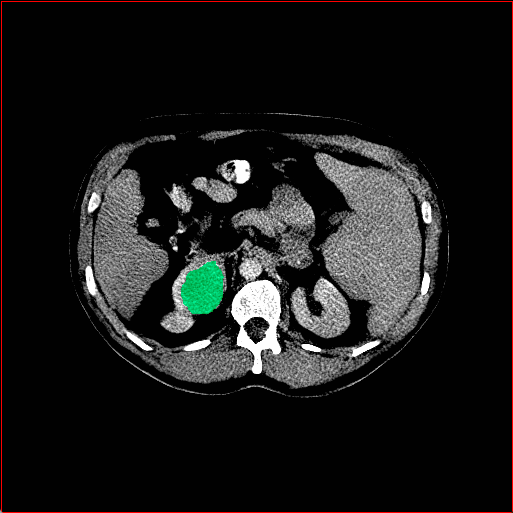

MAISI-v2 Controlnet qualitative Results:

Figure 5 shows qualitative results for MAISI-v2 Controlnet on 5 types of tumors.

Colon Tumor

0.75×0.75×1.50.75\times 0.75\times 1.5

mm

512×512×256512\times 512\times 256

Figure 5: MAISI-v2 segmentation-guided results for five types of tumors. We show results for different voxel spacing and volume size to demonstrate the flexibility of MAISI-v2. Different Hounsfield Unit window is used to better show the contrast between tumor and normal tissues.